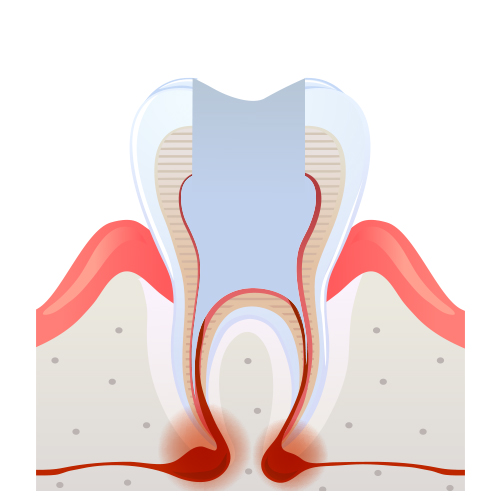

신경치료 과정

05

05

신경관 영구재료로 채움

06

06

치아등 머리부분을 레진으로 채우거나 기둥을 만듦